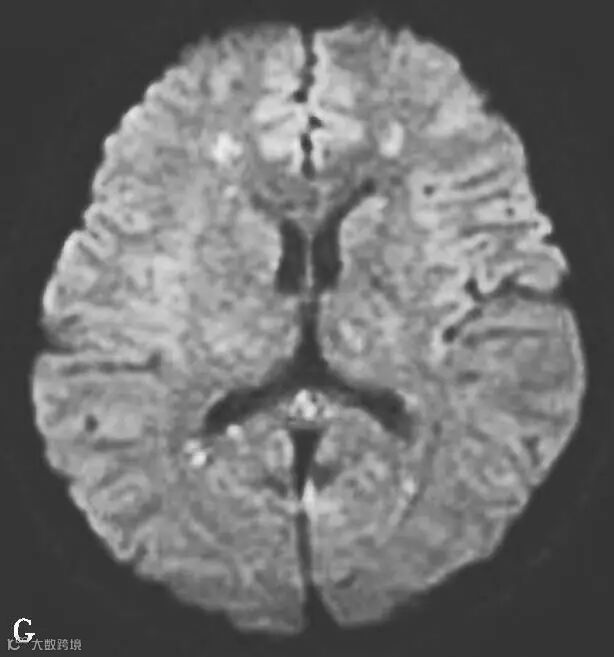

图6-11-2 弥漫性轴索损伤

男,36岁,外伤后2天。A~J(A、B.T2WI,C、D.T1WI,E、F.T2WI-FLAIR,G、H.DWI,I、J.ADC图):双侧额叶、半卵圆中心及胼胝体压部可见多发斑点状等T1稍长T2信号,边缘不清,FLAIR及DWI呈高信号,ADC图病灶信号减低 。